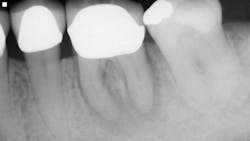

The first case involves a 49-year-old female. Tooth no. 31 had a deep periodontal probing on the straight buccal. The patient was warned that the tooth might be fractured, but she still decided on treatment (figure 1).

Calcium hydroxide paste medication was placed in the canals on three visits, each two weeks apart. Treatment included a total of six weeks of calcium hydroxide therapy.